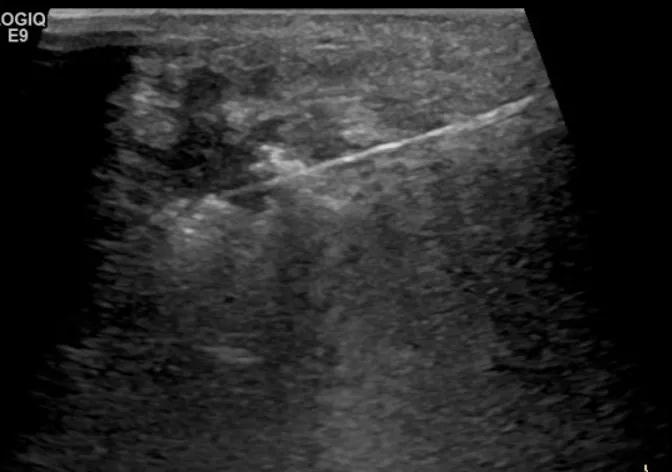

第四例是胸腺癌化妆包,术后、化疗之后淋巴结转移,肿块范围巨大,99mm*61mm,边界不清,呈浸润状,肿块包绕颈动脉,颈内静脉压闭,症状明显。由于患者放化疗也不敏感、血供非常丰富,于是采取多点姑息性消融。姑息性消融后未实现完全消融,病灶大片坏死,肿胀疼痛得到明显的缓解,后续患者未再来复查。

(病例4图例)